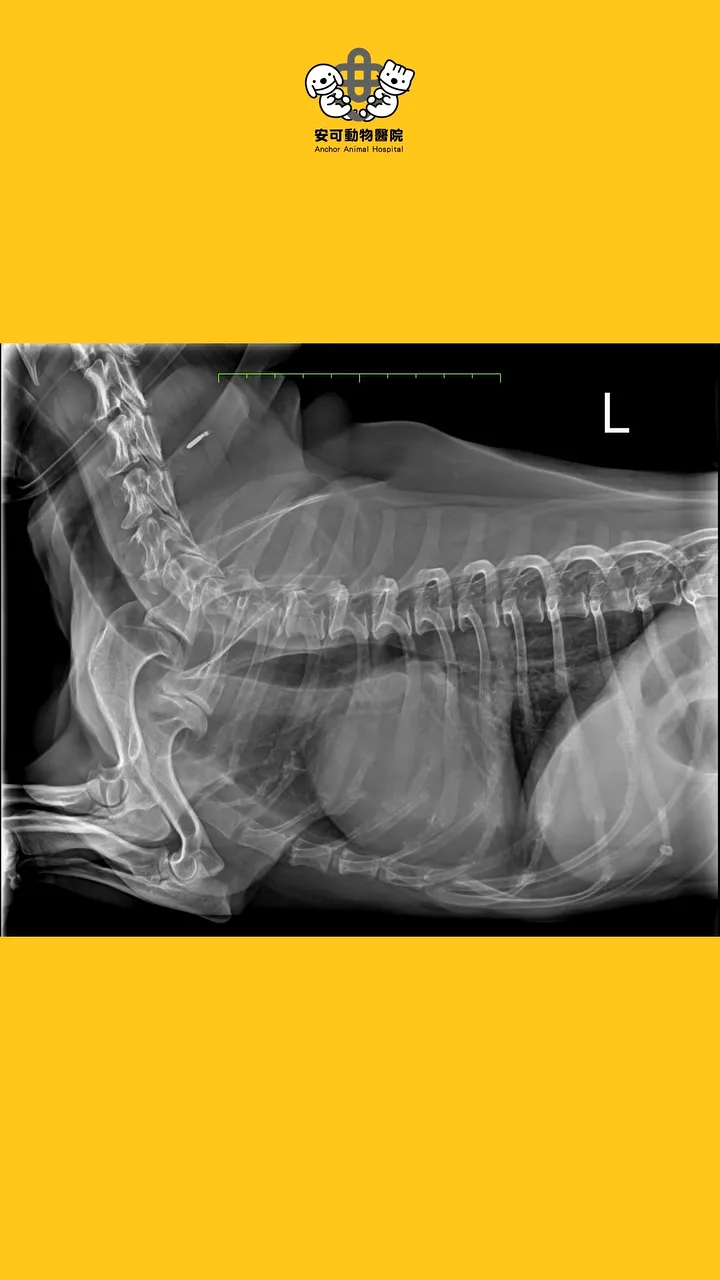

病例分享 毛孩的臨床症狀 1. 突然變很喘,伴隨間斷性劇烈咳嗽。 2. 精神食慾正常,於友院服用止咳藥物後,無顯著改善。 3. 腹部異常膨脹,於

當遇到毛孩有呼吸急促、會喘、咳嗽、呼吸困難等狀況時,安可的醫師腦海裡其實已經開始思考所有可能的原因,例如: 心臟問題、肺臟問題、胸膜腔壓迫性疾病、疼痛,抑或是其他生理性等問題,都一一跑過